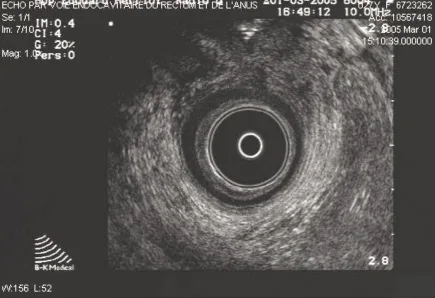

Le canal anal est étudié de haut en bas. Trois niveaux de coupe doivent être systématiquement repérés : coupe supérieure en regard du pubo-rectal (Fig. 1), coupe intermédiaire avec visualisation du SAI et du SAE (Fig. 2), et coupe inférieure avec présence exclusive du SAE.

Figure 2. Coupe au niveau du muscle pubo-rectal

Échoanatomie normale (Figs 1 et 2)

Nous décrirons l’aspect mis en évidence lors d’un examen réalisé avec une sonde rigide. L’interprétation des données anatomiques est complexe. Autour du cône apparaissent des couches concentriques hyperéchogènes et hypoéchogènes (Fig. 2).

La sous muqueuse correspond à la première couche hyperéchogène située directement au contact de la sonde [6].

Le SAI correspond à la première couche hypoéchogène homogène. L’épaisseur du sphincter interne est de 1,5 à 3 mm [6, 7].

L’interprétation du SAE est plus délicate. L’aspect admis par la plupart des auteurs est celui décrit dans l’article princeps de Sultan [8]. Le sphincter anal comporte au total trois couches

et le SAE correspond à la 3e couche

hyperéchogène discrètement hétérogène (située après le SAI). À la partie basse du canal seul le SAE est mis en évidence.On y distingue deux couches séparées par un fin liseré hypo-échogène correspondant à la couche circulaire interne et à la couche longitudinale externe.